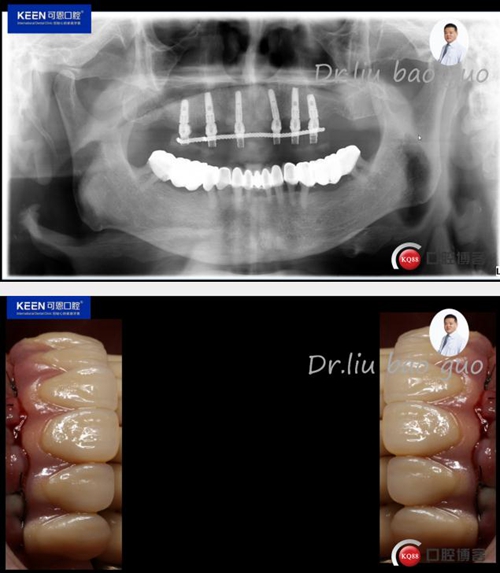

治療方案:建議上頜種植16,14,12,22,24,26,種植后即刻負(fù)重

術(shù)后照片

義齒試戴及戴入后照片